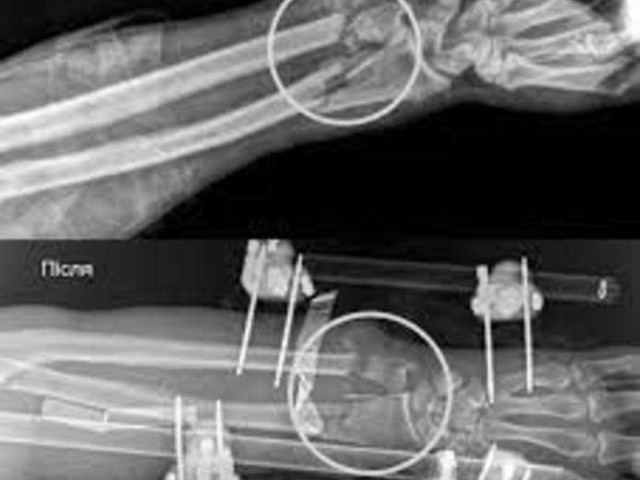

У Львові лікарі змогли зберегти руку 37-річному мешканцю області, який під час заготівлі дров майже повністю відтяв собі ліве передпліччя бензопилою. Історію чоловіка розповіли у Першому медичному об'єднанні Львова. Про це пише Медіа агентство АСС з посиланням на УП Життя.

Травма була критичною: рука фактично трималася лише на шкірі. В чоловіка були повністю пересічені артерії, пошкоджені кістки, м'язи, сухожилля та нерви. За порятунок кінцівки взялася мультидисциплінарна команда медиків.

Спершу ортопеди-травматологи стабілізували переломи за допомогою апарата зовнішньої фіксації. Далі судинні хірурги відновили кровопостачання, зшивши пошкоджені судини – саме цей етап був вирішальним, адже без циркуляції крові тканини швидко змертвіли б.

Завершили втручання аутодермопластикою – дефект закрили власною шкірою пацієнта.